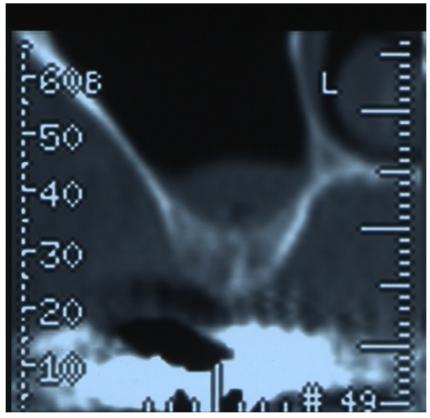

We report a 65-years-old female patient who came to our attention for the presence of an OAF and was treated using an autologous bone graft integrated by xenologous particulate bone graft. An expanded polytetrafluoroethylene titanium-reinforced membrane (Gore-Tex) was used in order to obtain an optimal reconstruction of soft tissues and to assure the preservation of the bone graft from epithelial connection.

我们报告了一位 65 岁女性患者,因存在 OAF 而就诊,我们采用自体骨移植物与异种颗粒状骨移植物相结合的方法进行治疗。使用膨体聚四氟乙烯钛增强膜(Gore-Tex)以获得软组织的最佳重建,并确保骨移植物免受上皮连接的影响。